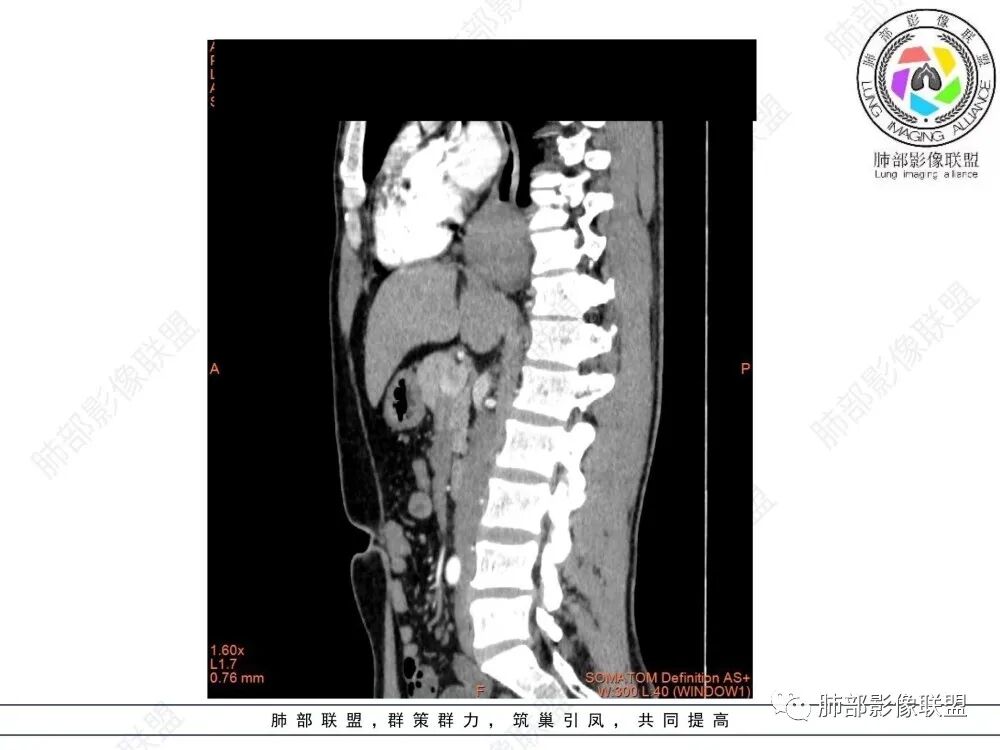

影像学特点:类纵隔区病变,沿食管生长,形态不规则,但边界清楚,内部信号/密度均匀,强化程度比较弱。

影像诊断思路:起源食管肿瘤(非黏膜起源,肌层起源),良性或低度恶性肿瘤可能性大,一般以神经鞘瘤、胃肠间质瘤及平滑肌瘤为主。食管神经鞘瘤强化明显均匀、以食管上段多见,周围常见炎性增大淋巴结,不太符合;胃肠间质瘤小的比较均匀,大的不均匀,但强化程度较高;影像上看这例病例比较符合平滑肌瘤。

食管平滑肌瘤是最常见的食管良性肿瘤,多见于男性,男女之比为2.6:1,高发年龄 30~60岁之间与食管癌相比,食管平滑肌瘤 的一个主要特点是病史相对较长,病情进展缓慢。病史最长者达10年余,平均 15.7个月,尽管病史较长,但大多数患者仍能进普食。食管平滑肌瘤的诊断一般比较容易,结合患者临床症状、食管造影及食管镜所见,一般均能得出正确诊断。食管造影主要为充盈缺损,病变与食管壁成锐角,粘膜线连续无破坏,管腔收缩扩张比较自如。钡餐造影敏感性高,但对食管壁间及食管周围情况难以判断。CT具有极高的密度分辨率,并且可以获得高质量的多平面重组图像,有利于食管壁间及食管周围情况的判断,表现为食管下段环绕管壁生长,偏心性或薄厚不均软组织密度肿块,密度均匀,内缘分叶状,管腔与正常食管壁构成不规则多角形扩张,增强动脉期无强化,多角度重建其病灶长轴与食管长轴不一致。由于食管壁在收缩状态下厚度约为5.6mm,扩张状态厚度不超过3mm,CT扫描时保持食管处于扩张状态可提高小病灶检出率。MR表现为T1加权等信号,T2加权稍高信号,可见高信号粘膜层,增强扫描轻度渐进性强化,密度均匀,无出血坏死。对于粘膜及周围脂肪间隙的判断具有明显优势。